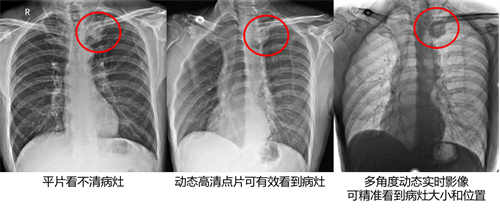

在实际工作中,由于静态DR摄影是二维影像,存在骨骼的重叠、拍摄位置及角度偏差、肢体旋转等局限,对病变细节的显示影响因素多,对于重叠病灶、微小模糊的病灶、隐匿性病灶等问题无法进行精准诊断,容易造成漏诊误诊。

由于静态DR的不可视化,在一些特殊的检查上,需要凭借医生的临床经验才能获取有效影像,例如寰枢关节正位摄影,常常需要多次摄影才能得到有效影像;骶尾椎摄影,常常会因为盆腔内容物而导致平片上观察不清楚;还有胸部正位,由于内脏的遮挡,也常会出现漏诊误诊等等。而动态DR依靠可视化瞬时高清点片,极速精准获取有效信息,同时可即时回放视频信息,可以有效降低误拍次数,获得更加精准的影像信息,减少患者不必要的射线剂量和因误拍造成的多次摄影的时间成本。